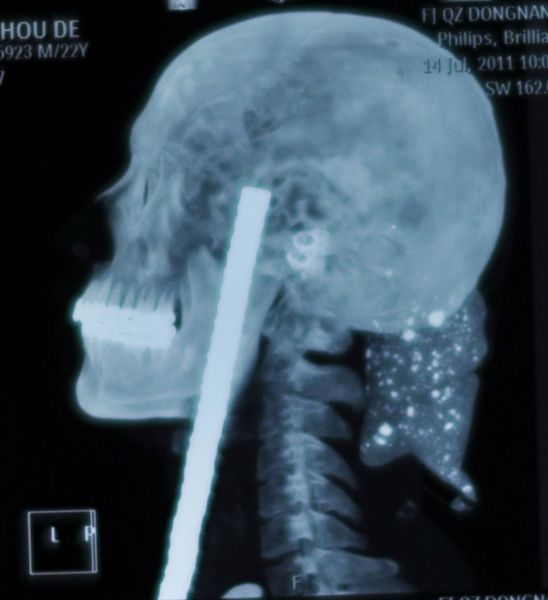

Wu Moude, 22, landed on a steel bar which penetrated 15cm into his head from beneath his chin. It took five hours of surgery to remove the bar, which saw surgeons cut open Wu's windpipe and skull.